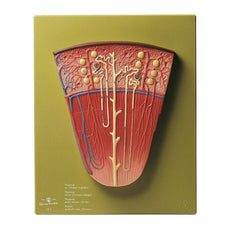

This Urinary System all-in-one-model shows:- Structures of retroperitoneal cavity

- Large and small pelvis with bones and muscles

- Inferior vena cava

- Aorta with its branches including iliacal vessels

- Upper urinary tract

- Rectum

- Kidney with adrenal gland.

One front half of a kidney is removable from the anatomical model of the urinary system. With easy to change male insert (bladder and prostate, front and rear half) and female insert (bladder, womb and ovaries, 2 lateral halves) the Urinary System model is a great teaching tool.